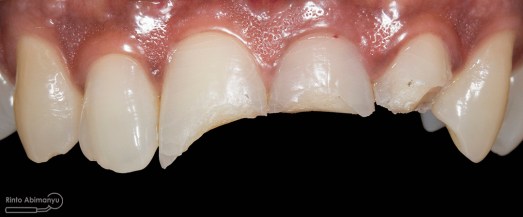

Kasus hari ini tentang gigi-gigi anterior yang fraktur karena kecelakaan lalu lintas. Pasien datang menceritakan kejadian yang dialaminya dan meminta saran bagaimana sebaiknya tindakan yang dilakukan pada giginya…

Begini kondisi klinis saat datang…